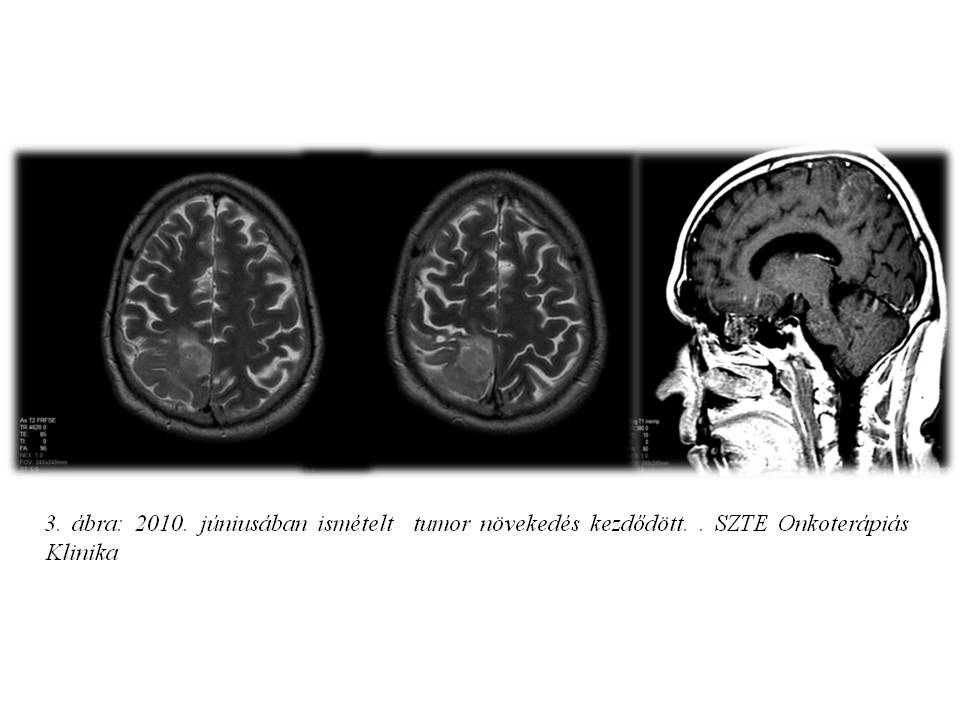

A 39 éves férfi betegnél 2004 nyarán jobb oldali parieto-occipitalis térfoglaló folyamatot detektáltak CT vizsgálattal, mely 2008 augusztusában növekedni kezdett (1. ábra). Az elvégzett biopszia grade II oligodendrogliomát igazolt. A beteg ezt követően definitív dózisú (22x1,8 Gy + 12x1,8 Gy) irradiációban részesült (2. ábra). 2 éven át fokozatos tumor regressziót, és stabil betegséget észleltünk, majd klinikailag stabil állapota mellett készült MR képalkotás 2010 júniusában tumor progressziót mutatott (3. ábra). Ekkor funkcionális MR és diffúzió súlyozott tractographia alapján neuronavigációs éber műtét során a makroszkópos tumor eltávolítása megtörtént. A hisztopatológia ekkor anaplasticus irányba transzformálódó, grade II-III oligodendrogliomát írt le. Posztoperatív 20x1,6 Gy dózisú reirradiáció történt, majd temozolomide monoterápia indult, mely 23 cikluson keresztül folytatódott (4. ábra). Ismételt tumor progresszió miatt 2012 szeptemberében betegünk reoperáción esett át, recidiváló, grade III-IV malignusan transzformálódó oligodendroglioma diagnózisával. A mozgásrehabilitáció mellett bevacizumab monoterápia indult egyedi méltányossággal, melyet 2013 júliusában kontroll MR által leírt subacut bevérzés miatt 4 ciklust követően a beteg kérésére felfüggesztettünk (5. ábra), 10 hónap viszonylagos jó állapot után gyors progresszió, majd 2014.06.27-én exitus következett be.